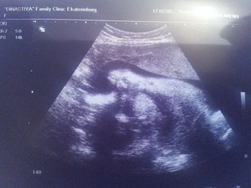

1) Вчера ходили на УЗИ. Врач сказал что все все у нас хорошо:))) Наш мальчик (а о том что будет мальчишка мы узнали еще на 21-ой неделе, чему несомненно были рады) лежит правильно и весит уже почти 2 кг ( а если быть точнее 1972гр). ПДР поставили нам на 31 декабря

"новогодний подарочек" будет. Вообщем посмотрели мы малыша, а ему это явно не нравится, ведь как и на прошлом УЗИ он закрыл свое личико ручками и отвернулся вот так: